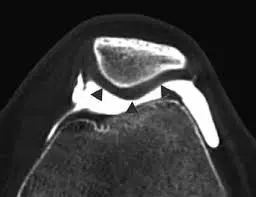

Artrotomografia (ArtroTAC) en Caracas: Información, Precios y Beneficios La artrotomografia o ArtroTAC es un procedimiento avanzado de diagnóstico por imágenes